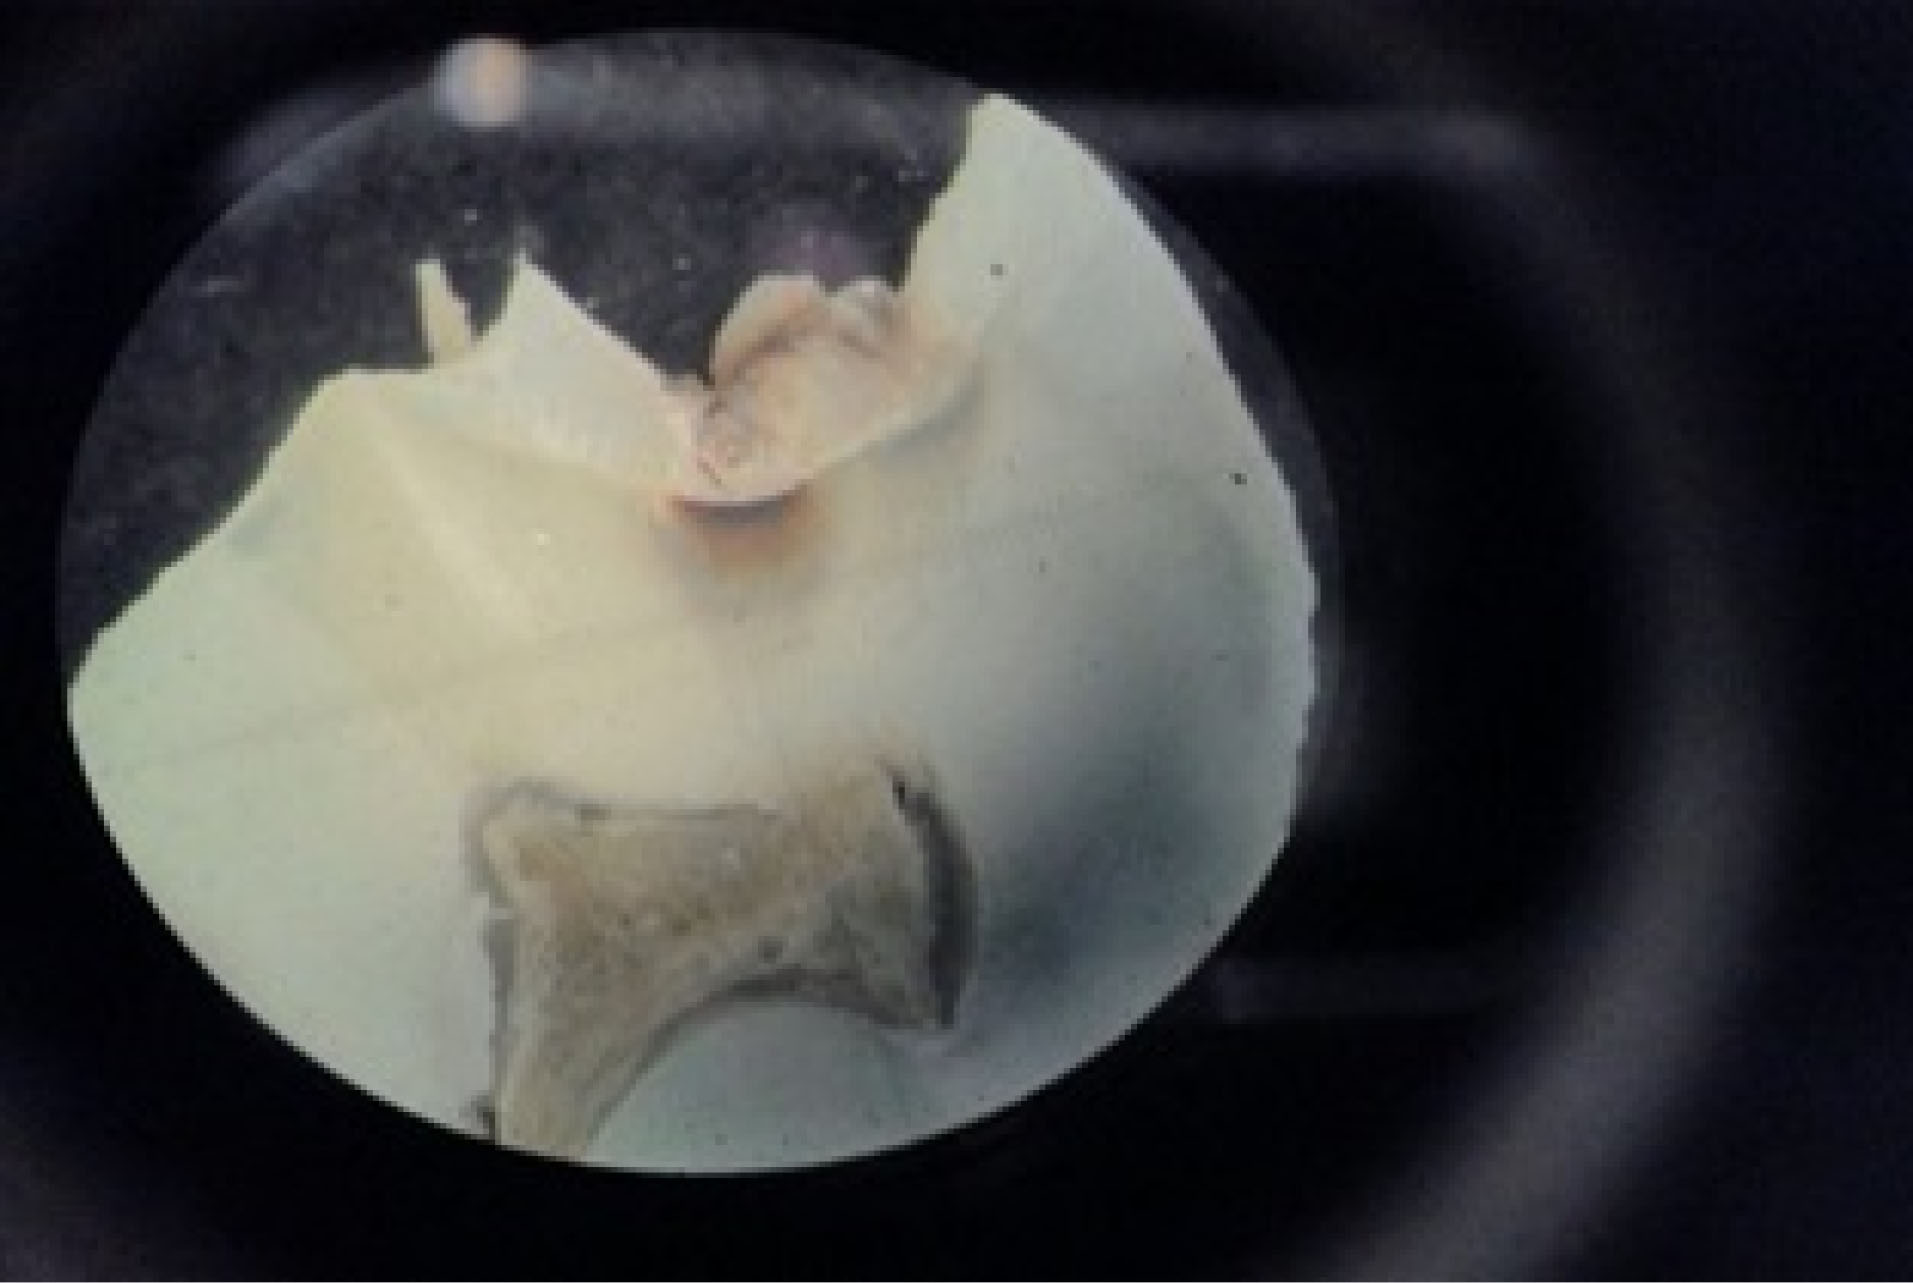

Subsequently, the tooth sections were viewed under a stereomicroscope using magnification by a pathologist (), and the sound and carious occlusal enamel and dentin were recorded in tables prepared to this end. Finally, the observers’ diagnoses were compared with the histopathological diagnosis as the gold standard.

Figure 2.

A sample of cross-sections under a stereomicroscope.